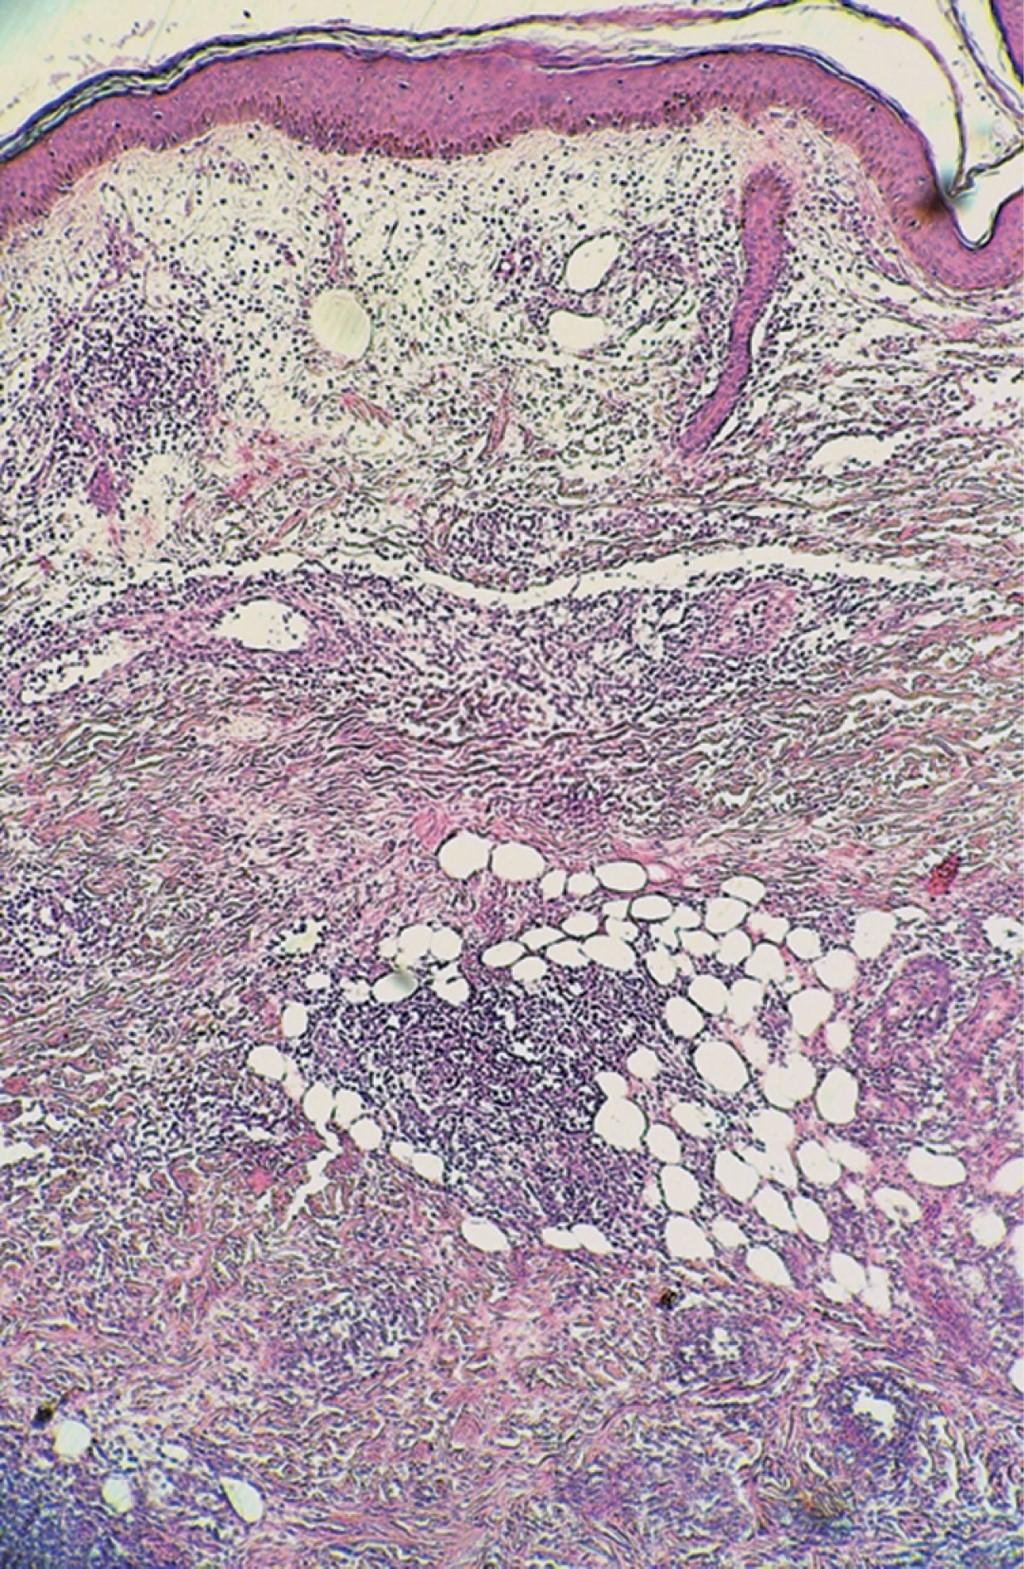

Se realiza biopsia incisional y el estudio histopatológico con tinción de rutina muestra: epidermis atrófica con hiperqueratosis ortoqueratósica, formación de tapones córneos e hiperpigmentación de la capa basal. En algunas zonas de la dermis superficial se observa la presencia de edema entre las fibras colágenas así como infiltrados moderados focales que tienden a rodear algunos vasos dilatados y congestionados. Estos infiltrados aumentan en intensidad y se observan ocupando la dermis media y profunda, e incluso hasta tejido celular subcutáneo. Están constituidos por abundantes histiocitos vacuolados, mismos que son más evidentes en las partes profundas del corte; además se aprecian linfocitos, histiocitos y numerosos polimorfonucleares que se ubican de manera predominante en las partes profundas de la epidermis y tejido celular subcutáneo, disponiéndose al nivel de los lóbulos grasos. Se aprecia edema en algunos sitios de la dermis profunda. Los infiltrados también tienden a rodear en algunos sitios a fibras nerviosas engrosadas. La tinción para bacilos fue positiva (Figuras 4, 5 y 6).

Figura 1